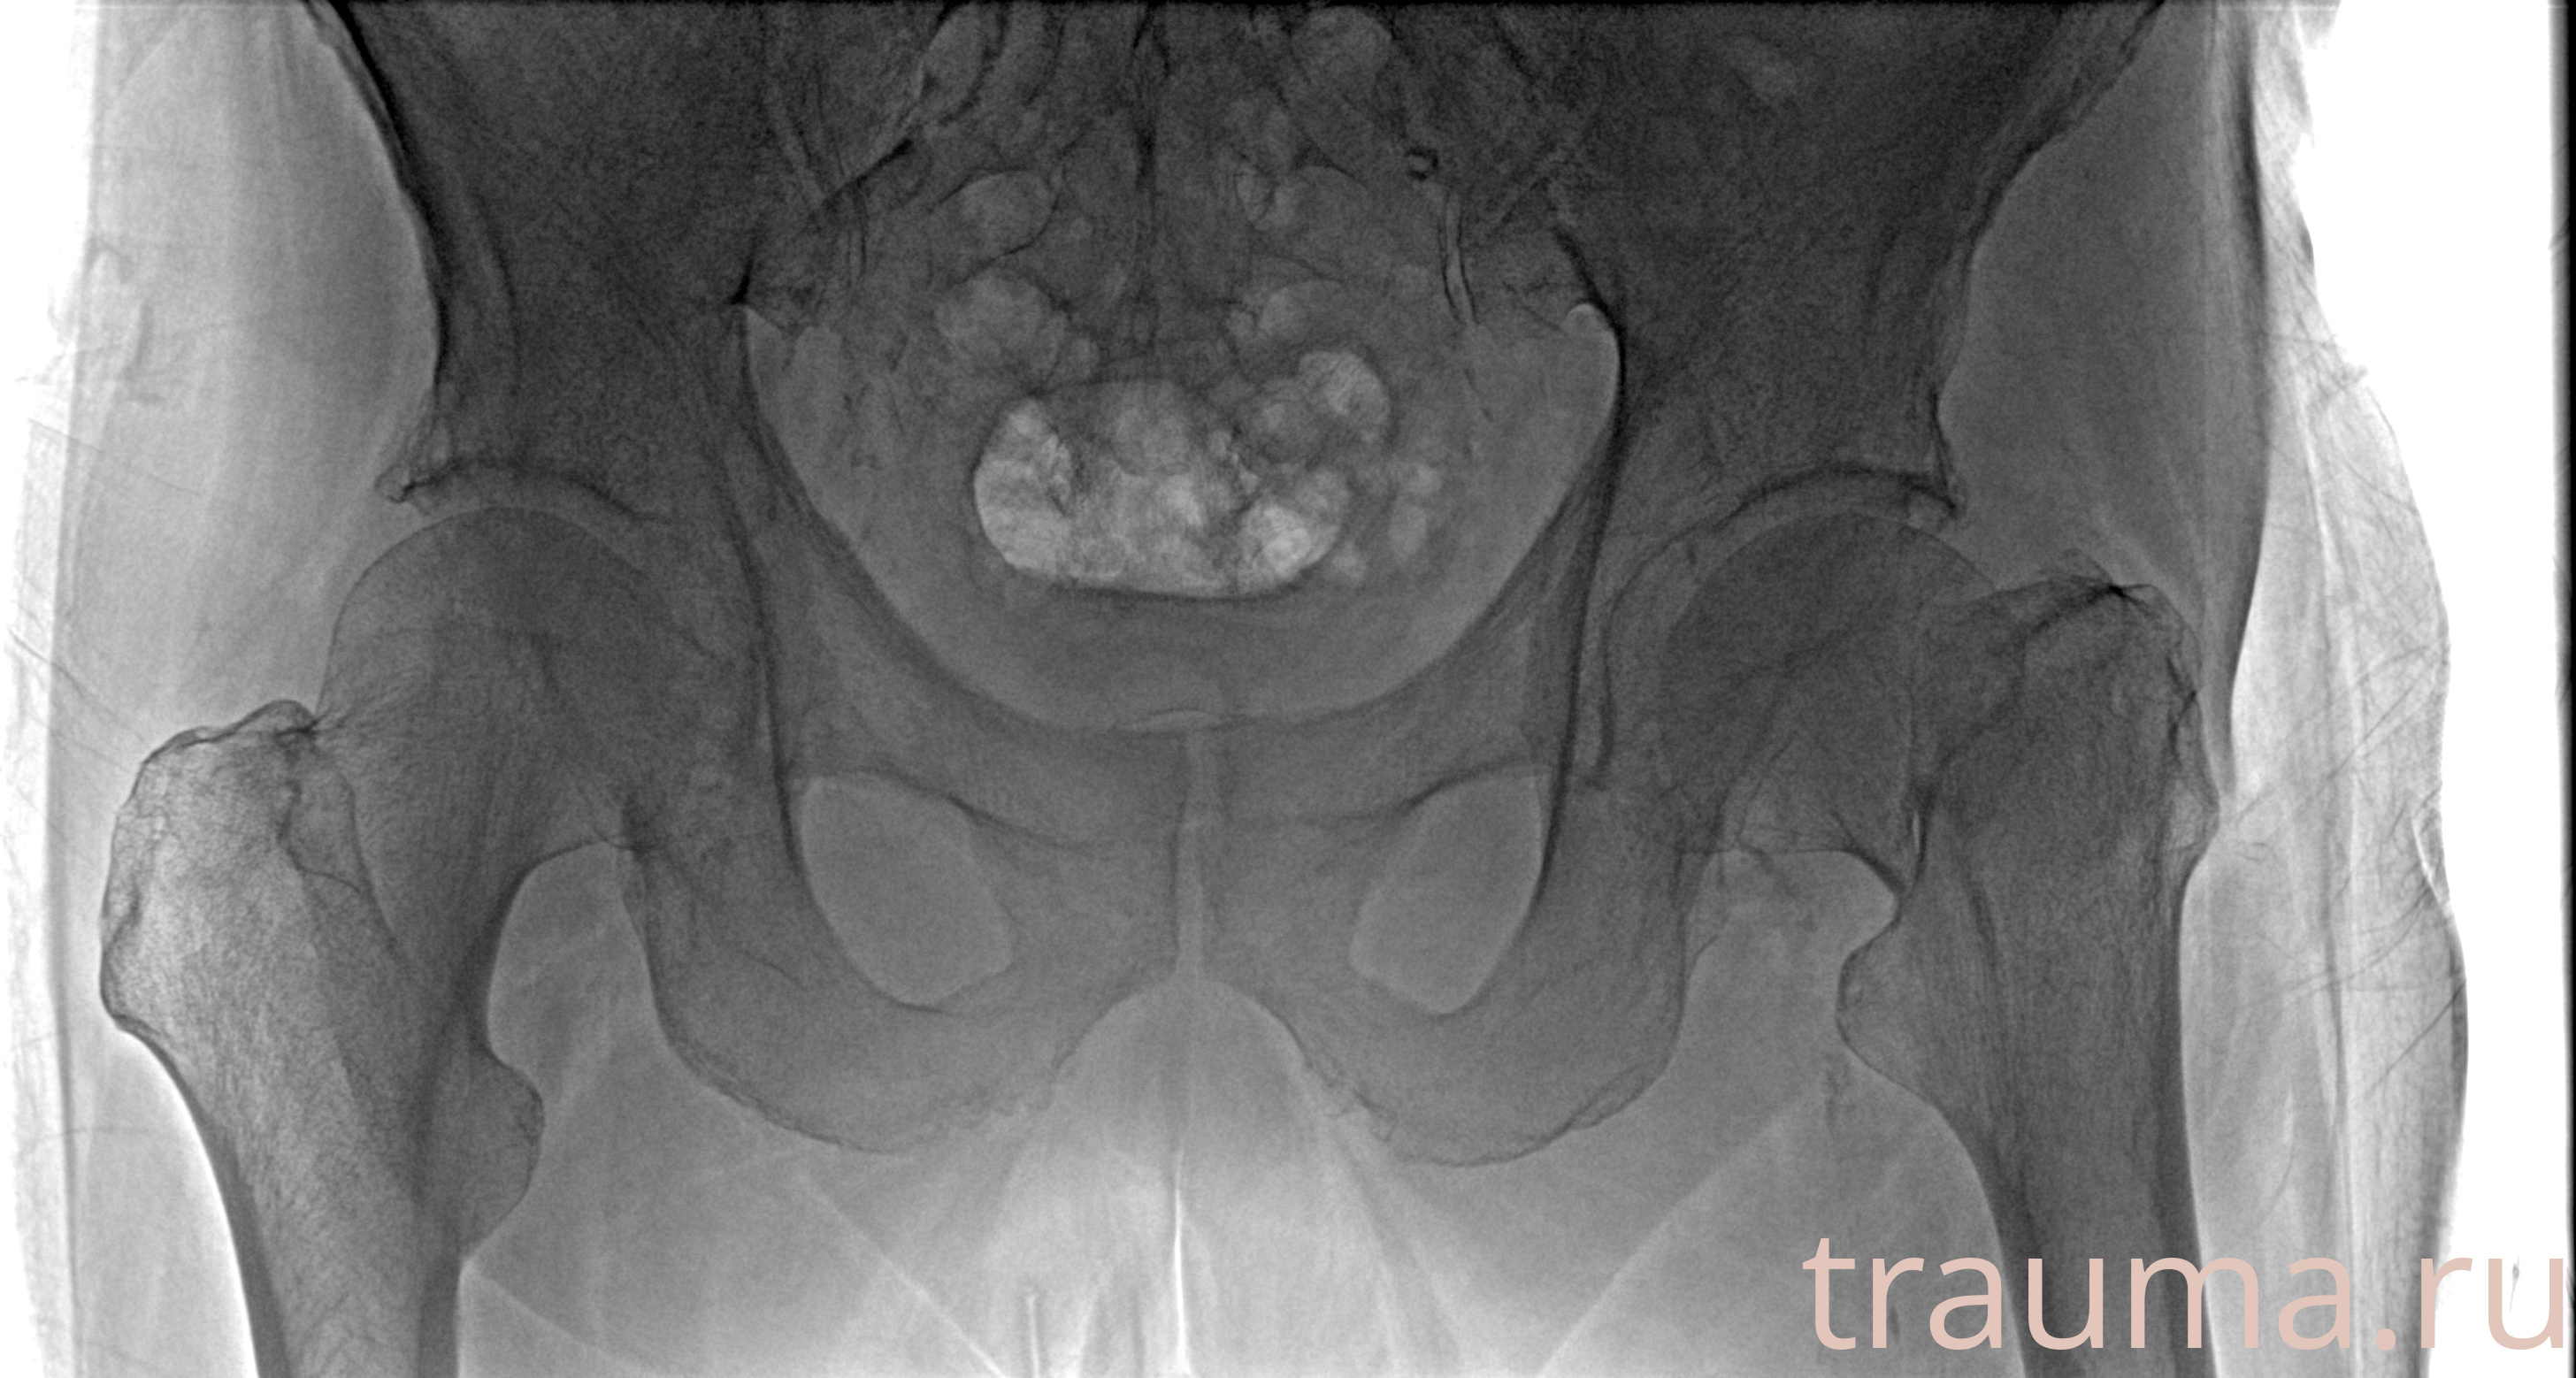

Рентгенограммы

Рентген на дому: по вашему адресу приезжает врач-рентгенолог, травматолог-ортопед с мобильным рентгеновским аппаратом, проводит диагностику травмы или заболевания, делает необходимые рентгенограммы, дает рекомендации по дальнейшему лечению. Получить качественные снимки в домашних условиях возможно благодаря уникальной методике, разработанной МосРентген Центром для института  Склифосовского